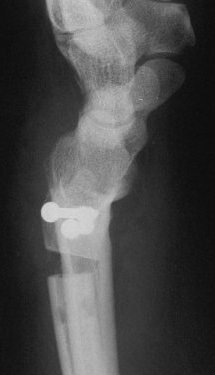

Case 2. Minimal Madelungs picture following pediatric distal radius fracture.